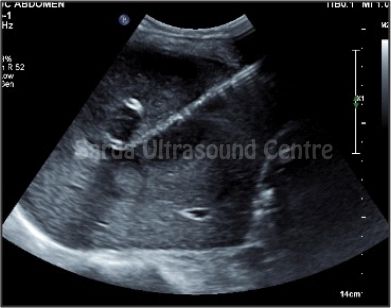

Our facility offers comprehensive range of ultrasound-guided interventions such as FNAC, biopsies, injections and aspirations, ensuring precise and safe treatment for our patients.

With Detailed pre-procedure councelling, High resolution ultrasound machines, Significant experience in using ultrasound for guided procedures, maintainance of sterile environment ensuring highest level of safety; we are committed to providing the highest standard of care for all ultrasound guided interventions.